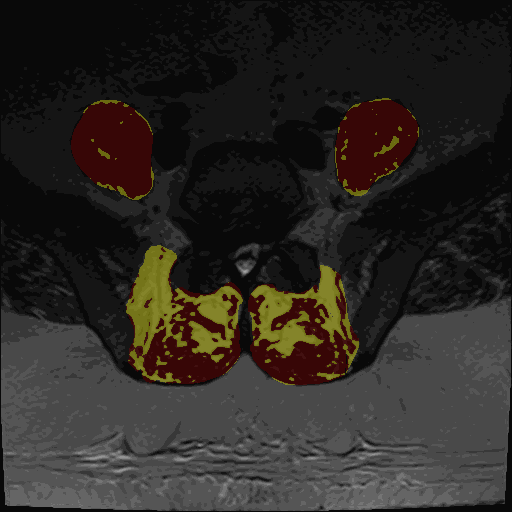

Animated example of MuscleMap muscle quantification

• Thresholding maps for either GMM or Kmeans and two or three clusters

The thresholding maps can be loaded as a segmentation to visually check thresholding accuracy